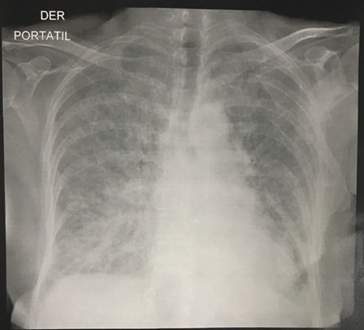

Se realiza electrocardiograma (Figura 1) y radiografía de tórax (Figura 2).

Figura 2: Radiografía de tórax. Radiopacidades tipo reticular y alveolar en los cuatro cuadrantes con predomino basal derecho.

Es importante resaltar que este tipo de tumores se presentan inicialmente sin síntomas y sin signos al examen físico 18. Una amplia variedad de sintomatología clínica dificulta su diagnóstico oportuno, pues puede debutar como alguna complicación cuando el tumor ha alcanzado grandes tamaños o simular algún cuadro de otra patología cardiovascular 5, como sucedió en esta paciente. Pinede y cols documentaron signos de insuficiencia cardiaca en el 43%, dolor torácico o infarto de miocardio en el 30%, anemia en el 13%, trastorno de repolarización en el electrocardiograma en el 21%, edema pulmonar en la radiografía de tórax en el 27% 20. Sin embargo, en esta serie no se describen algunos hallazgos evidenciados en la paciente como es la asociación entre mixoma auricular y presencia de hiponatremia como en este caso, por lo cual el mecanismo de hiponatremia puede ser explicado por la falla cardiaca, de otro lado la elevación de Dímero D ha sido descrito incluso sin diagnóstico de embolia pulmonar 21, de la misma manera la presencia de edema pulmonar 22 y asociación con hipertensión pulmonar severa ha sido reportada en casos aislados asociada con obstrucción del orificio de la válvula mitral 23, clasificada como hipertensión pulmonar del grupo 3, siendo potencialmente reversible a las 6 semanas posteriores al procedimiento quirúrgico 24.